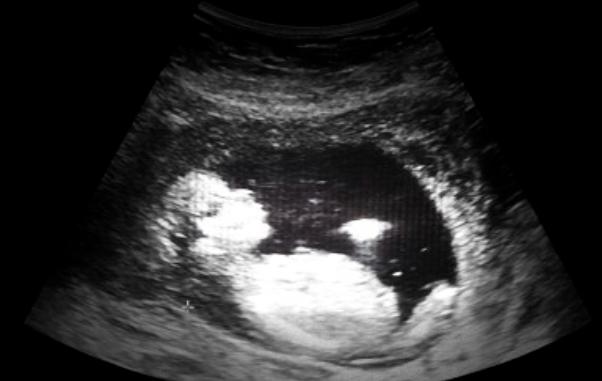

私人试管婴儿治疗(IVF)是指利用助孕怀孕的技术将母亲的卵子和精子放入一个培养室中,使精子结合卵子形成怀孕卵,再将怀孕卵移植到民主自己体内的一种治疗方式,目前已成功解决了许多夫妻不孕的问题。但在接受私人试管婴儿治疗的过程中,有一些注意事项需要重视。